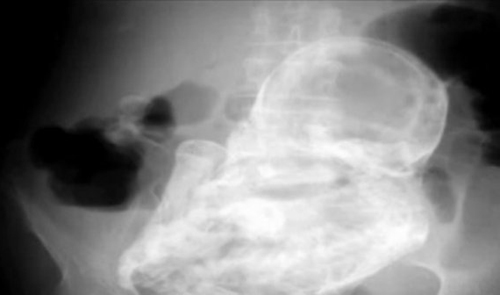

It was only when medics x-rayed her they discovered the calcified foetus or lithopaedian inside her body.

An initial ultrasound revealed nothing before a radiographer discovered a tumour in her abdominal cavity.

Lithopaedian, also known as stone baby, is a rare syndrome that can occur when the foetus implants outside the uterus.

If the baby becomes too large to be absorbed back into the body, it undergoes a process of mummification, with barriers of calcium protecting the mother from the decaying foetus.

The stone baby can then remain undiagnosed for decades. There are fewer than 300 cases reported in medical literature.